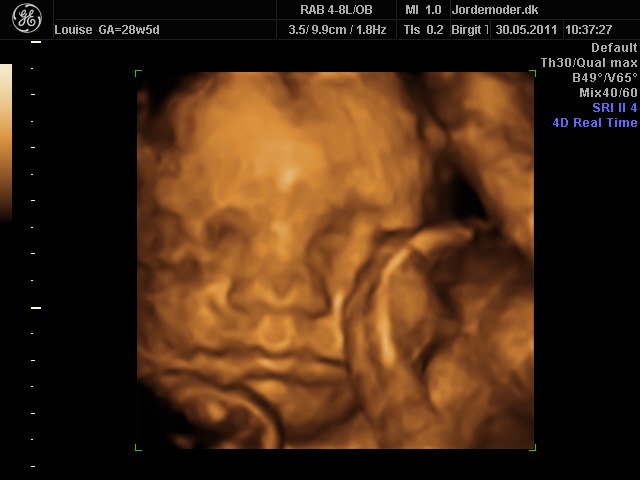

Så kom vi til 3d scanning igår. Lillepigen er slet ikke så stor som egen Jm kønnede hende HELDIGVIS! 1500 gram ca vejer hun nu, 28+6....

Hun har den fineste mund, jeg er helt misundelig på de smukker læber hun har.¨Ja hun er jo alt i alt bare dejlig, og jeg har ikke engang set hende sådan helt rigtig endnu.... Også har hun nogen gode runde kinder....

I skal ikke snydes for billeder af vores lille skønhed...